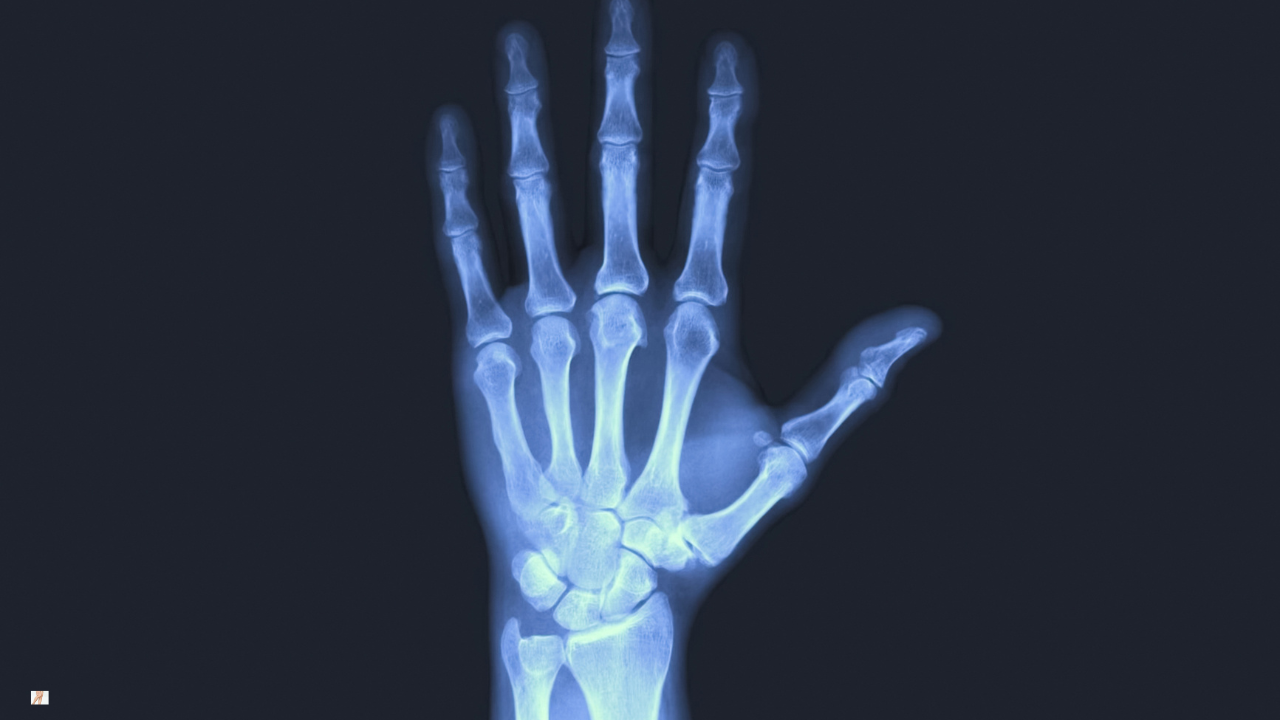

Plain X-ray can confirm structural change within the joint. Findings may include joint space narrowing, osteophyte formation, subchondral sclerosis or altered joint alignment. In the thumb CMC joint, dorsal subluxation may be visible in more advanced stages.